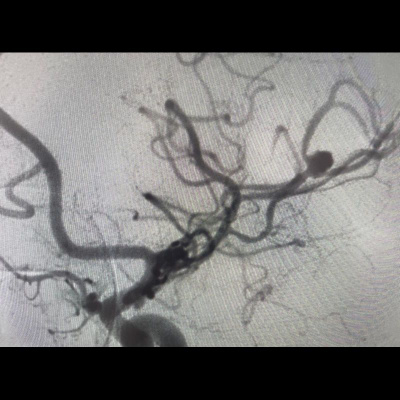

40 yaş, K

Ateş, bir haftadır artan baş ağrısı, yeni gelişen bilinç bulanıklığı

Sol MCA Segmet M2-3’te Sakküler Mikotik Anevrizma Rüptürü